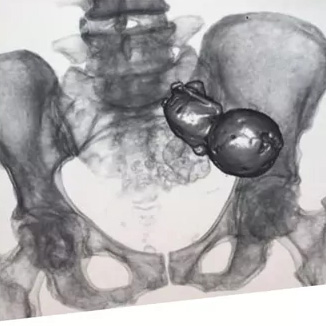

母体を守るために死んだ胎児は石灰化される。

コロンビアにて、腹痛のため病院にやってきた77歳の女性の体内から石灰化した胎児を発見した画像。

死亡した胎児の体が大きすぎる場合は体に再吸収されず、異物反応の一部として外側を石灰化し、母体を感染から守る働きが起きる。